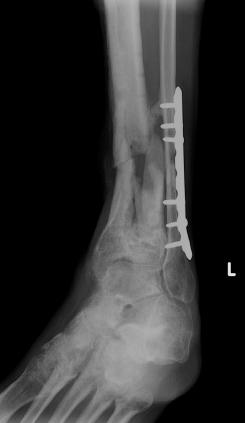

Post-infection X-Rays of the damaged right & left legs / ankles

After the last surgery Liam developed Staphylococcal (staph) infection as well as Osteomyelitis on the bone. Liam went to the ER of

Tempe St. Luke with a temperature of over 104 degrees and severe pain of the left leg. Liam was released from the ER with a diagnosis of

Gastroenteritis and instructions to follow up with a visit to Dr. Armendariz. Four days later and with a continued very high temp, Liam was

seen by Dr. Armendariz. Dr. Armendariz immediately performed 3 surgeries to clean out the infected areas of both the left and right leg and

to place wound vacs on the damaged areas of the legs.

An interesting point to note, as it applies to the second and third x-rays (from the left), is the placement of the last screw at the bottom

of the right legs fibula plate. Notice how Dr. Keller completely missed the plate. Not only is the screw useless, but it has started protruding

in such a way as to cause severe pain and require padding to keep from bursting through the skin. A later surgery is planed for the screws

removal.